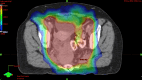

Figure 8

Figure 8. Axial PET with RT planning overlay demonstrating dose (as color wash) from 30 Gy (in blue) to 59.4 Gy (red), which is the prescription dose to the PET-positive lymph nodes.

RT: radiation tomography; PET: positron emission tomography